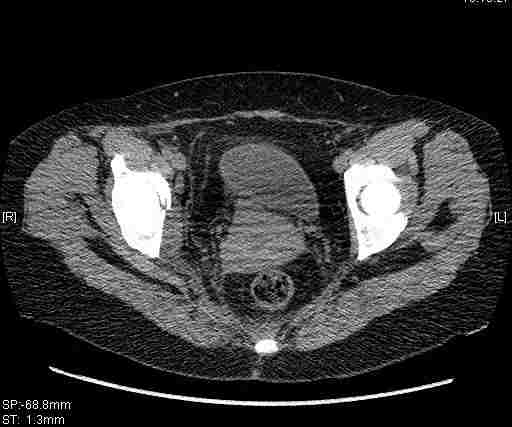

Удалось сегодня вывести пациентку в соседнюю больницу, где есть кт. Срезы сделаны только горизонтальные.

|

Приветствую,Антон.Рункова рядом нет,но после полученных данных КТ,обсуждали совместно.Итог обсуждения-развернутый ответ дать не получится,т.к.срезы выбраны не информативные.Если ориентироваться на данные 3D,то ,ИМХО,можно лечить на вытяжении.